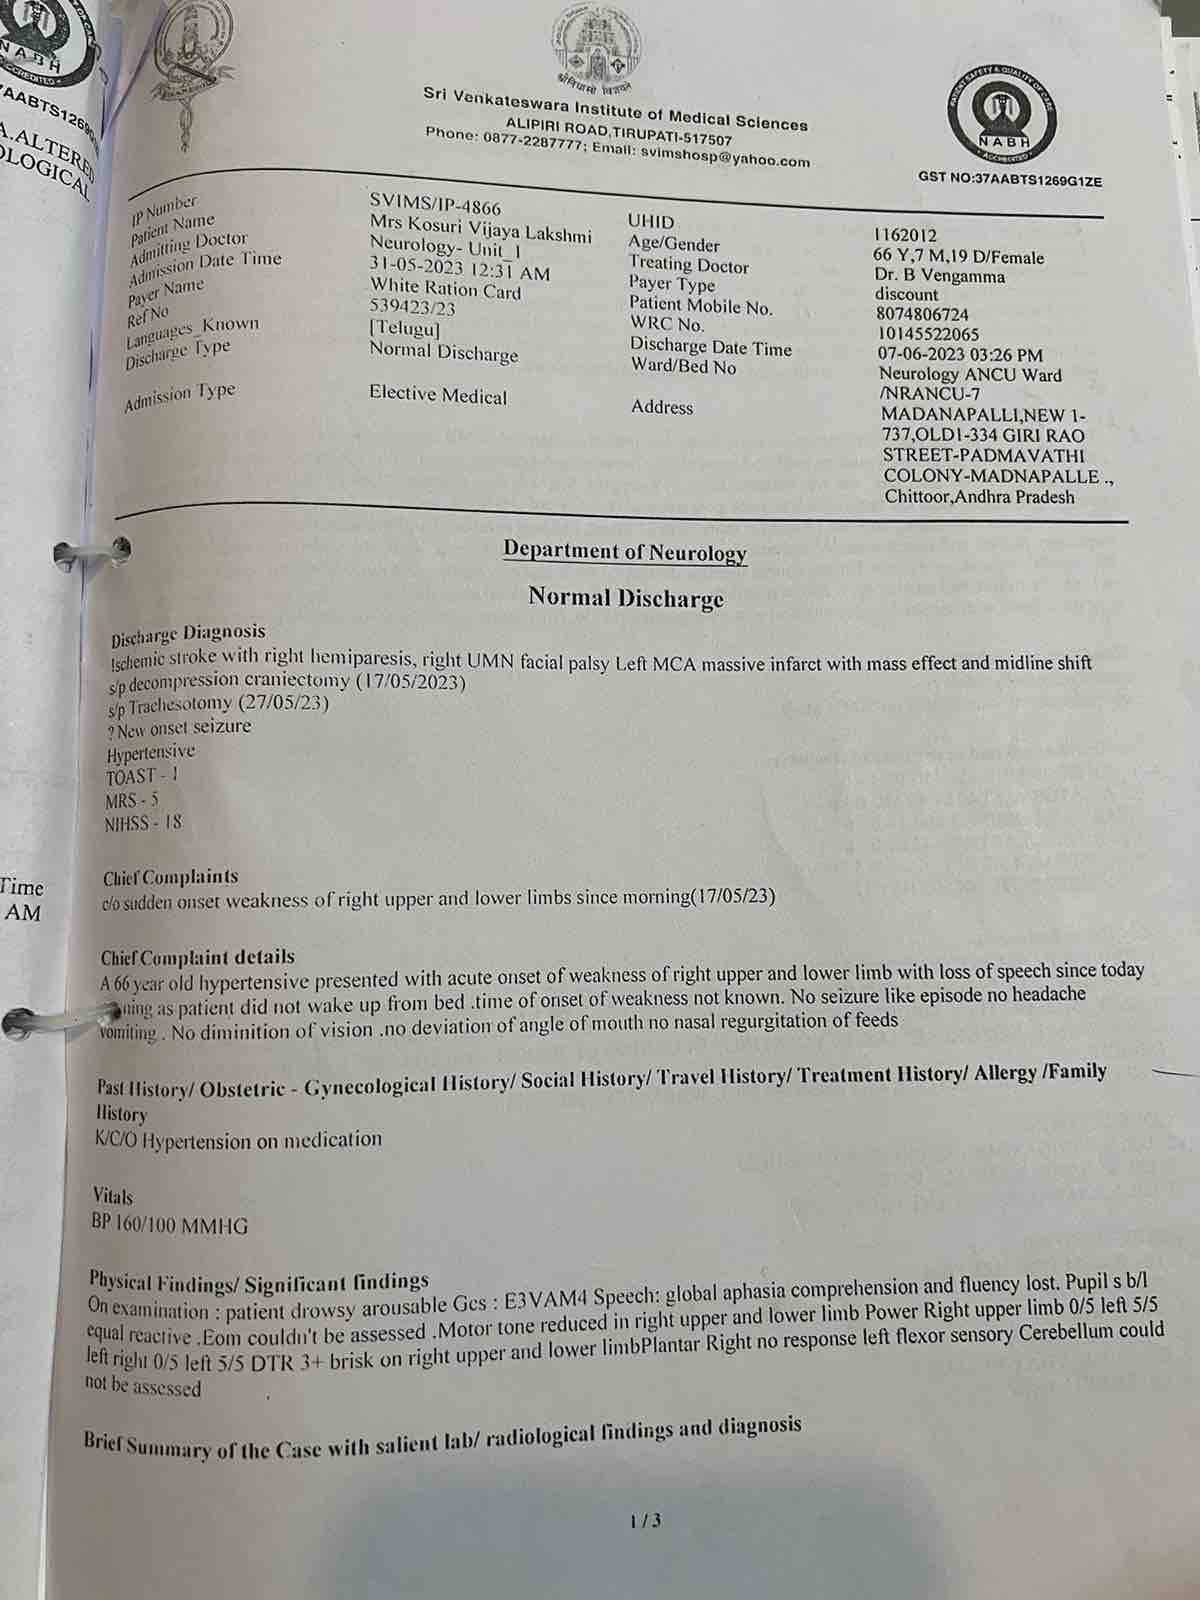

We are reaching out to you today with a heavy heart and a plea for help. Our beloved 66-year-old mother K VIJYA LAKSHMI, has been facing an incredibly challenging journey since 16th May when she had brain stroke & underwent emergency brain and abdomen surgery. Her recovery has been a rollercoaster of ups and downs.

During her hospitalization, she endured multiple complications, including respiratory distress, recurrent severe infections, and even seizure-like activity. Through it all, she has shown immense strength and determination. Still she require three more surgeries to stand on the path of recovery.